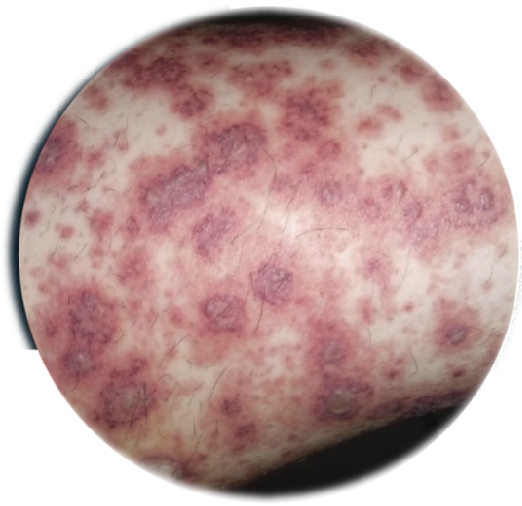

Paciente del sexo femenino, de 49 años de edad, que ingresó al servicio de urgencias del Hospital Regional Universitario de Colima, Colima, México, el 27 de septiembre de 2022 debido a edema ascendente de miembros inferiores hasta abdomen, acompañado de dolor articular en región lumbar, rodillas y muñecas, todo ello con 15 días de evolución. Dos días antes de su ingreso, notó la aparición de lesiones máculo-papulares en ambos muslos (figura 1), acompañadas de prurito y dolor quemante difuso, así como debilidad progresiva que le impidió deambular. Como antecedentes refirió ser diabética, manejada con metformina oral. Refirió haber tenido 2 partos vaginales eutócicos, el último hace 13 años.

Figura 1 Lesiones cutáneas en muslos y biopsia de piel (hematoxilina-eosina)

A su ingreso, la paciente se encontró pálida, postrada en cama sin poderse incorporarse, con presión arterial de 120/70 mmHg, frecuencia cardíaca de 90 latidos por minuto, temperatura de 36.6 °C y un peso de 92 kg, con índice de masa corporal de 30%. Presentaba anasarca, con predominio del edema en miembros inferiores. El examen de fondo de ojo no mostró datos de retinopatía diabética ni otras lesiones. La exploración orofaríngea reveló úlceras blanquecinas dolorosas en paladar duro. Cuello y tórax no presentaban alteraciones de relieve. Se encontró discreta ascitis y dolor a la palpación profunda en epigastrio. En ambos muslos se observaron placas eritematosas e hiperqueratósicas, de distribución difusa y bordes bien definidos. En las extremidades se halló reducción de la fuerza muscular (Daniel’s 3/5) y dolor a la movilización articular, sin datos de flogosis ni otras lesiones dermatológicas. Los pulsos estaban presentes y eran de buena intensidad, con una saturación de O2 de 94%.

Respecto a las lesiones dérmicas, aunque no se observaron cambios histológicos propios de vasculitis (figura 1), nos parece claro que este fenómeno formó parte de la propia vasculitis sistémica, semejante a lesiones similares ya descritas11.